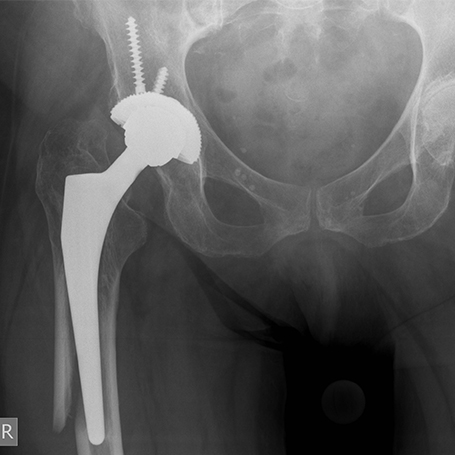

PERIPROTHETISCHE FRAKTUR

Brüche, die rund um bereits eingebrachte künstliche Gelenke entstehen, werden als Periprothetische Frakturen bezeichnet. Sie sind durch die Lagebeziehung zu dem jeweiligen künstlichen Implantat gekennzeichnet und können nach dem Unified Classification System (UCS) eingeteilt werden.

Bei einer immer älter werdenden Bevölkerung und der steigenden Anzahl von künstlichen Gelenken ist eine zunehmende Anzahl solcher Brüche zu beobachten. Ungefähr 3/4 der periprothetischen Frakturen entstehen durch Niedrigenergie- und Bagatelltraumata in Verbindung mit lokalen Risikofaktoren, wie Implantatlockerung, oder systemischen Risikofaktoren, z.B. Osteoporose.

Unterschieden werden die unterschiedlichen Verletzungstypen insbesondere im Hinblick auf die Stabilität der einliegenden Gelenkkomponenten. Bei Brüchen mit noch stabilen Gelenkkomponenten ist eine reine Knochenbruchversorgung (Osteosynthese) unter Berücksichtigung der Verankerungsmöglichkeiten im Knochen möglich.

Bei Ausbruch und damit Destabilisierung der Gelenkkomponenten muss ein Wechsel der Gelenkkomponenten und die gleichzeitige Stabilisation des Bruches durchgeführt werden.

Ziel der chirurgischen Therapie ist die zeitnahe Operation und die sofortige Vollbelastung. Hierfür stehen verschiedene Implantate bzw. Revisionsprothesen zur Verfügung. Die Kenntnis des einliegenden Implantates (Prothesenpass) ermöglicht ein angepasstes Vorgehen.